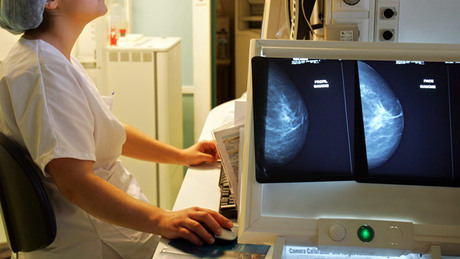

Women should get a mammogram every two years starting at age 50 — and while routine screening brings little benefit in the 40s, beginning it that early should be a personal choice, a government task force said Monday.

Also, there's not enough evidence to tell if new 3-D mammograms are the best option for routine screening, or if women with dense breasts need extra testing to find hidden tumors, the U.S. Preventive Services Task Force concluded.

The draft advice issued Monday is largely a rewording of the task force's controversial 2009 recommendation that drew protests for questioning the usefulness of mammograms in the 40s. The American Cancer Society has long recommended annual mammograms starting at age 40 and while insurance usually pays for them, experts feared the dueling guidelines would confuse the public.